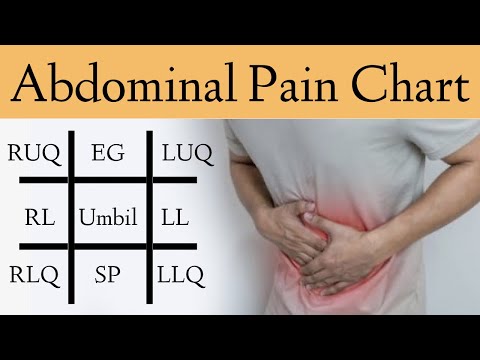

Abdominal Pain Differential Diagnosis

This video highlights different causes of abdominal pain according to the site of the pain in the abdomen. This is the first in a series of #shorts describing different causes of abdominal pain. DISCLAIMER: This or associated videos are not meant for self-diagnosis or a means of avoiding qualified medical care. Strictly for information only.

Abdominal Pain Causes by Location and Quadrant [Differential Diagnosis Chart]

🔥 Causes of Abdominal Pain in 60 SECONDS! [Differential Diagnosis by Location & Quadrant]

Differential Diagnosis of Abdominal Pain